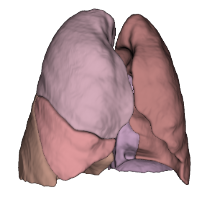

Lung Lobes

Anatomical segmentation

Pulmonary segments

Anatomical segmentation